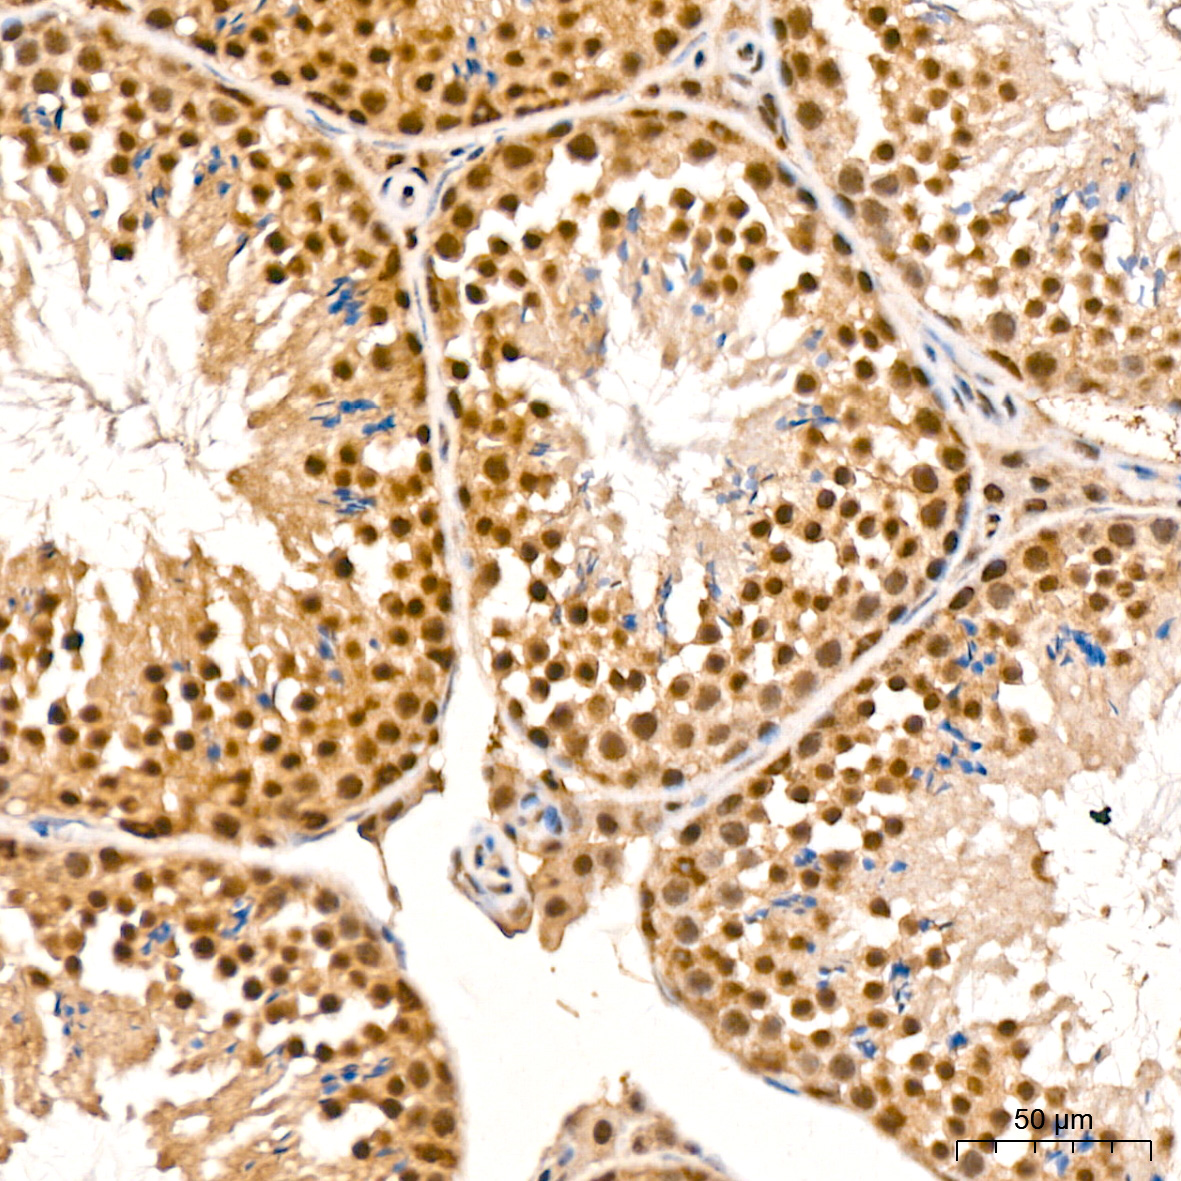

肿瘤细胞增殖是肿瘤细胞在体内或体外不断分裂和增加其数量的过程。正常情况下,细胞增殖是组织生长和修复的正常生理过程,但当细胞失去正常的生长调控机制,可能导致异常的细胞增殖,形成肿瘤。

肿瘤细胞是在基因水平上以不受控制的方式生长和分裂,侵入正常组织和器官并最终扩散到全身。这些细胞在代谢、形态、功能上与其来源的正常细胞或多或少的不同。肿瘤细胞增殖与异位受体或激酶(如 Bcr-Abl、EGFR、HER2、c-Met 和 Raf),组成型激活信号转导通路(如 PI3K/Akt 通路、MAPK 通路、Wnt 通路、Hippo 通路)和转录调节剂(c-myc、Smads、STATs、YAP)有关。